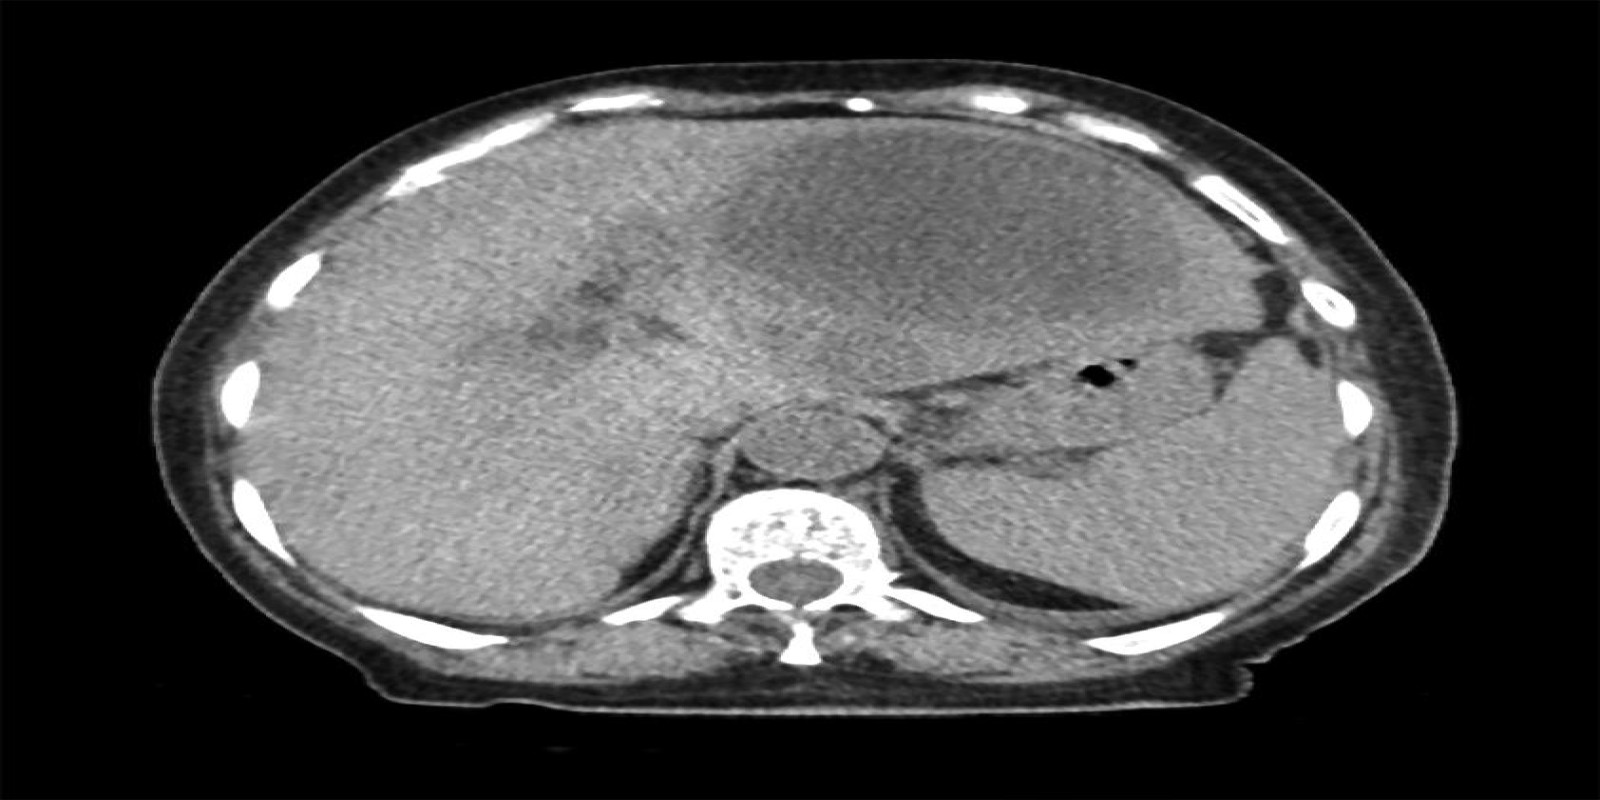

Caso Código 042G de Abscesso Hepático

Cod.: 042G